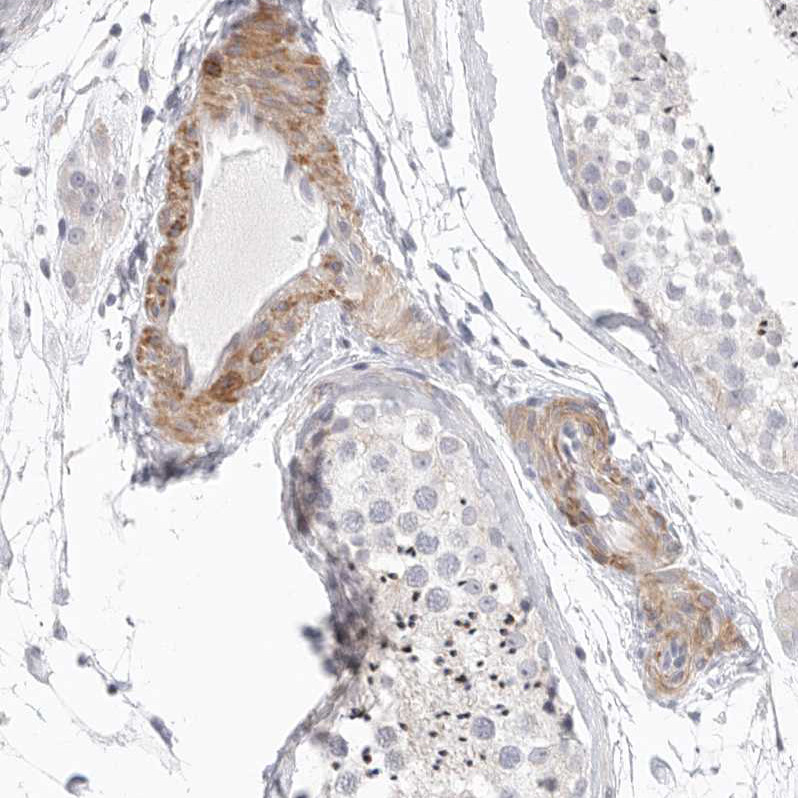

Immunohistochemistry analysis in human spleen and cerebral cortex tissues using HPA026871 antibody. Corresponding STAB2 RNA-seq data are presented for the same tissues.